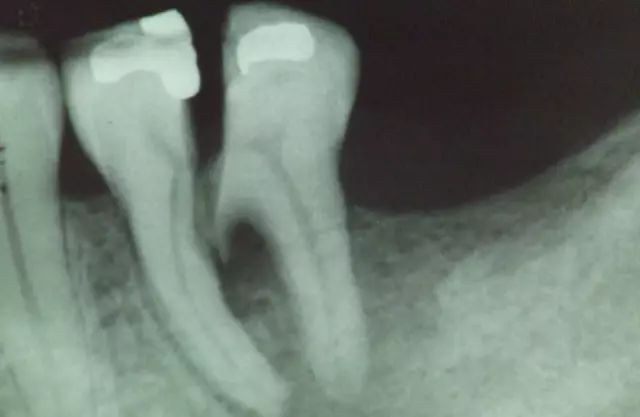

牙齿开裂,医学专业名称是牙隐裂,又称“不全牙裂”或“牙微裂”,它是牙冠表面的一些细小、不正常的裂纹。

电镜下的牙齿表面隐裂纹

②如果牙齿裂得严重,已经伤害到牙神经,需要做根管治疗后再用牙冠来进行牙齿保护。